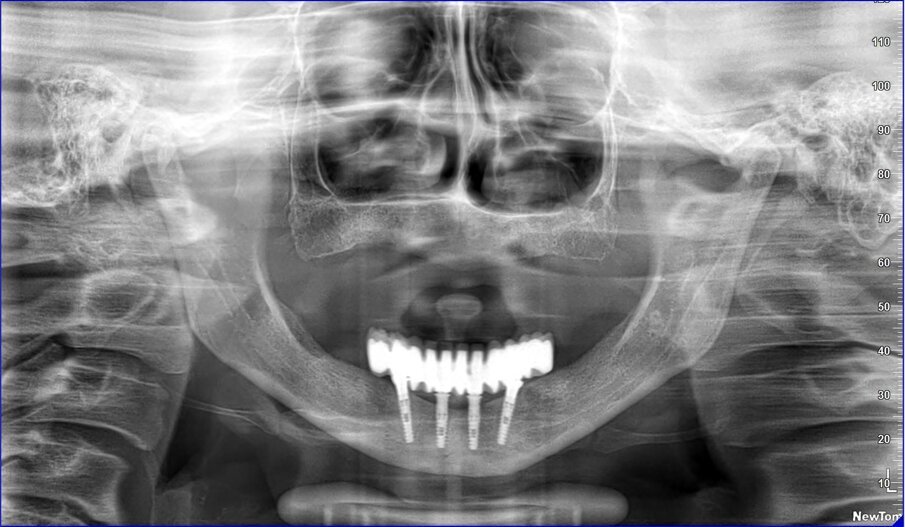

La resina alla stato ancora tenero va indurita con la lampada polimerizzante per alcuni minuti; una volta controllata la masticazione anche senza la chiave articolare e fatti gli opportuni minimi ritocchi, la protesi va rimossa e rifinita a dovere, poi riaccoppiata. Una OPT di conferma serve per verificare il corretto alloggiamento delle cappette sui monconi e la passività del manufatto.

Le tabelle 1-8 mostrano, su un totale di 313 impianti eseguiti tra arcata superiore (208) e inferiore (105), che la tecnica non ha alcuna complicanza biologica a 3 anni di esecuzione, non sono stati evidenziati fallimenti implantari in arcata inferiore (18 pazienti), solamente 5 in arcate superiori tutti nella zona molare (29 pazienti). In 1 paziente è stata registrata una frattura della protesi dovuta a eccessiva distanza tra gli impianti (zona laterale superiore e tuberosità) con antagonista naturale senza presenza di molari; 3 fratture dei denti in pazienti con bruxismo e serramento; circa la metà dei casi (140 impianti) è stata eseguita in condizione post-estrattiva e alcuni casi sono stati caricati con metodiche avanzate di rialzo di seno mascellare (11 pazienti) e 1 con Split Crest. Tutti gli impianti sono stati caricati immediatamente, anche quelli nei settori posteriori superiori o nella tuberosità.